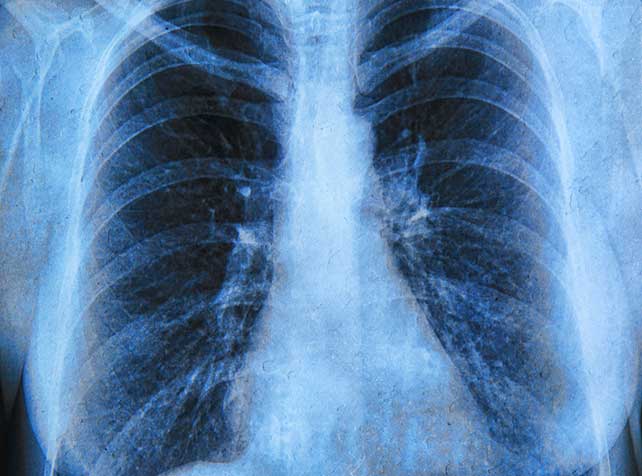

Doctors are concerned patients with lung cancer may be overlooked amid coronavirus AAP - 18-01-2023

Doctors are worried patients with lung cancer may be overlooked amid the focus on diagnosing and treating the coronavirus, which has similar symptoms.

New research shows unequal on Victoria's lung cancer treatment AAP - 20-02-2020

Research presented at the Australian Lung Cancer Conference shows the times to access treatment vary greatly between private and public health care.